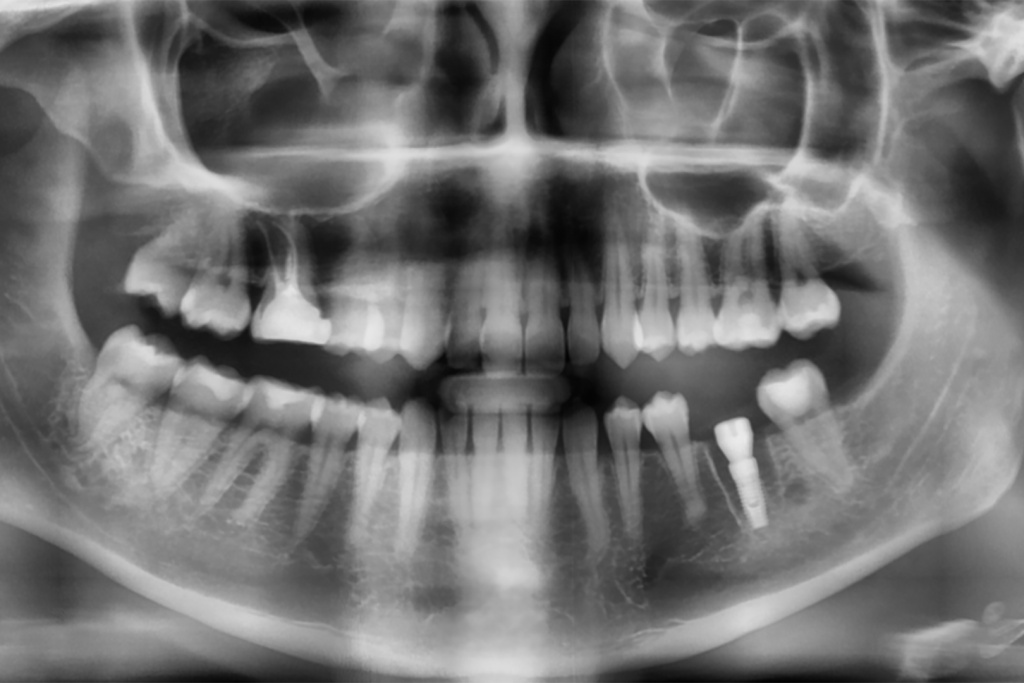

Одномоментная установка дентального имплантата, система Impro

Одноэтапная установка формирователя десны